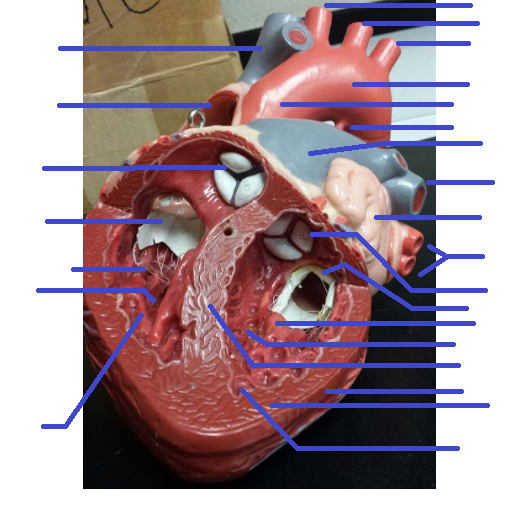

Name the missing parts.

Heart frontal section